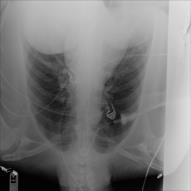

Thoracic diseases are very serious health problems that plague a large number of people. Chest X-ray is currently one of the most popular methods to diagnose thoracic diseases, playing an important role in the healthcare workflow. However, reading the chest X-ray images and giving an accurate diagnosis remain challenging tasks for expert radiologists. With the success of deep learning in computer vision, a growing number of deep neural network architectures were applied to chest X-ray image classification. However, most of the previous deep neural network classifiers were based on deterministic architectures which are usually very noise-sensitive and are likely to aggravate the overfitting issue. In this paper, to make a deep architecture more robust to noise and to reduce overfitting, we propose using deep generative classifiers to automatically diagnose thorax diseases from the chest X-ray images. Unlike the traditional deterministic classifier, a deep generative classifier has a distribution middle layer in the deep neural network. A sampling layer then draws a random sample from the distribution layer and input it to the following layer for classification. The classifier is generative because the class label is generated from samples of a related distribution. Through training the model with a certain amount of randomness, the deep generative classifiers are expected to be robust to noise and can reduce overfitting and then achieve good performances. We implemented our deep generative classifiers based on a number of well-known deterministic neural network architectures, and tested our models on the chest X-ray14 dataset. The results demonstrated the superiority of deep generative classifiers compared with the corresponding deep deterministic classifiers.